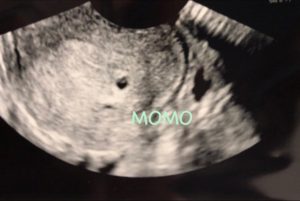

更に1週間後、病院でエコーをしてもらいました。

…Σ(‘◉⌓◉’)

いた!

真ん中のまるが胎嚢です。

まだ4週程の大きさとのこと。

先生からも週数が足りなかっただけで正常妊娠ですねと言って貰えて安心しましたし、凄く嬉しかったです。

エコーで見る我が子は可愛くとても嬉しかったのは2人目でも変わりませんでした。